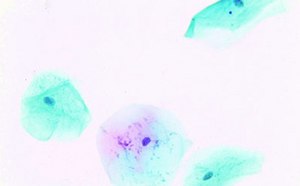

일반 조직학 및 조직병리학을 위한 일반 및 특수 조직학 염색제, 대조군 슬라이드, 기타 염색 공급품의 전체 제품군을 확인해 보십시오.

연구 및 임상 시료의 세포화학 염색제와 관련해서 모든 단계에 사용할 수 있는 종합적인 염색제와 시약 중에서 선택할 수 있습니다.